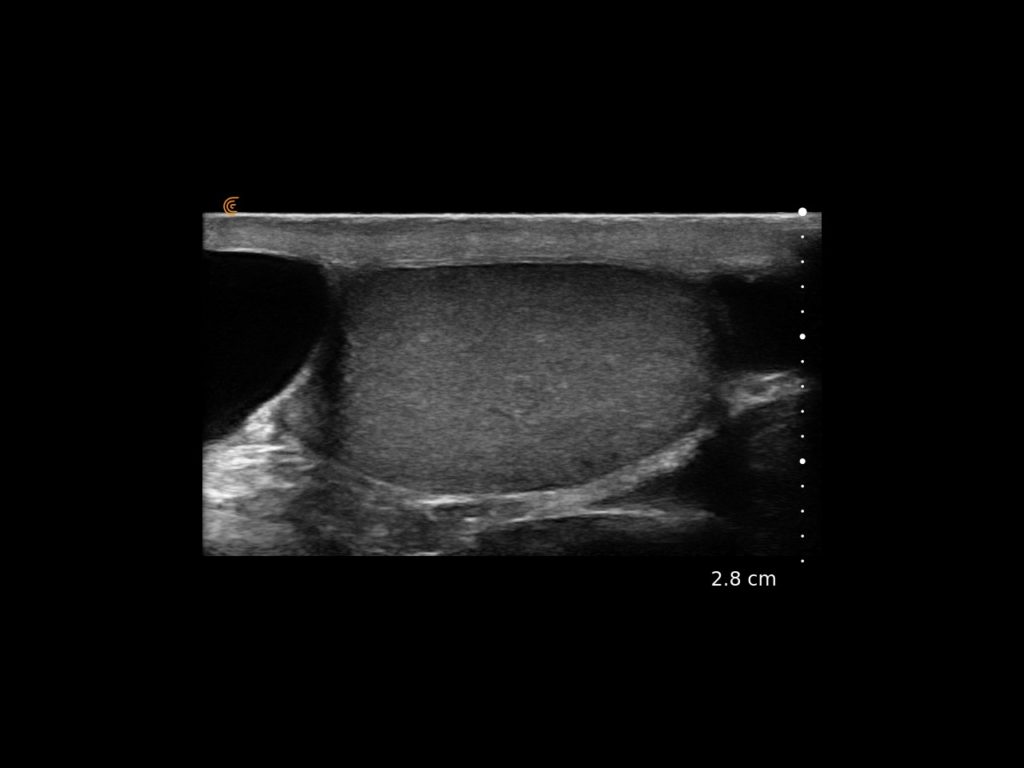

T-Mode es un enfoque innovador para la educación en ecografía diseñado para mejorar sus habilidades de escaneo utilizando la potencia de la inteligencia artificial en aplicaciones de Estética y Cirugía Plástica. Cette technologie novatrice superpose des couleurs distinctes, des motifs et des étiquettes pour identifier et différencier les structures anatomiques et les couches de tissu.